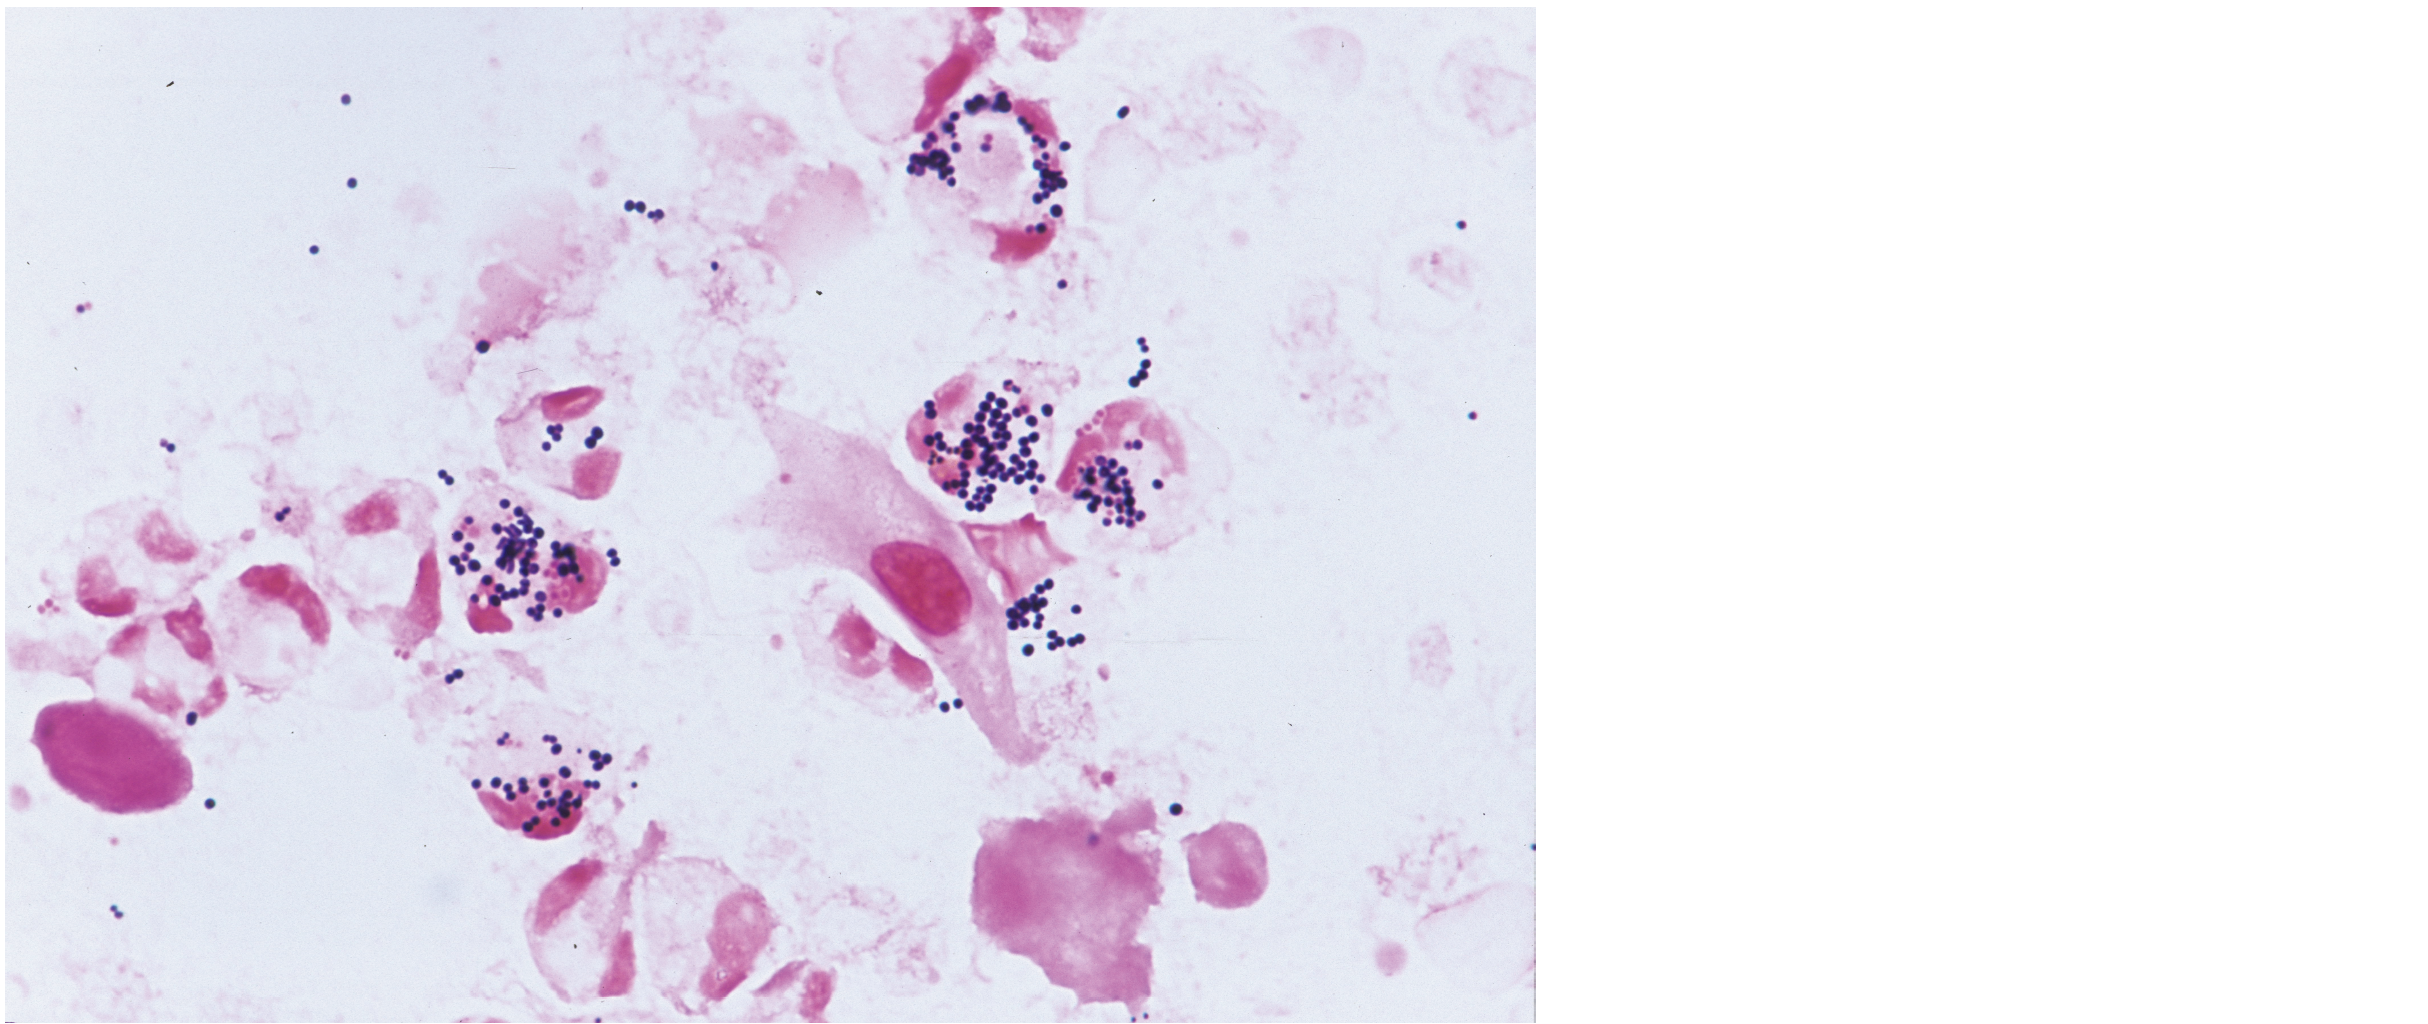

膿のGram染色標本を示す。分離菌はヒツジ血液寒天培地およびBTB乳糖寒天培地に発育し,カタラーゼ試験は陽性でマンニトールを分解した。推定される菌種はどれか。

Enterococcus faecalis

Staphylococcus aureus

Staphylococcus epidermidis

Streptococcus agalactiae

Streptococcus pyogenes